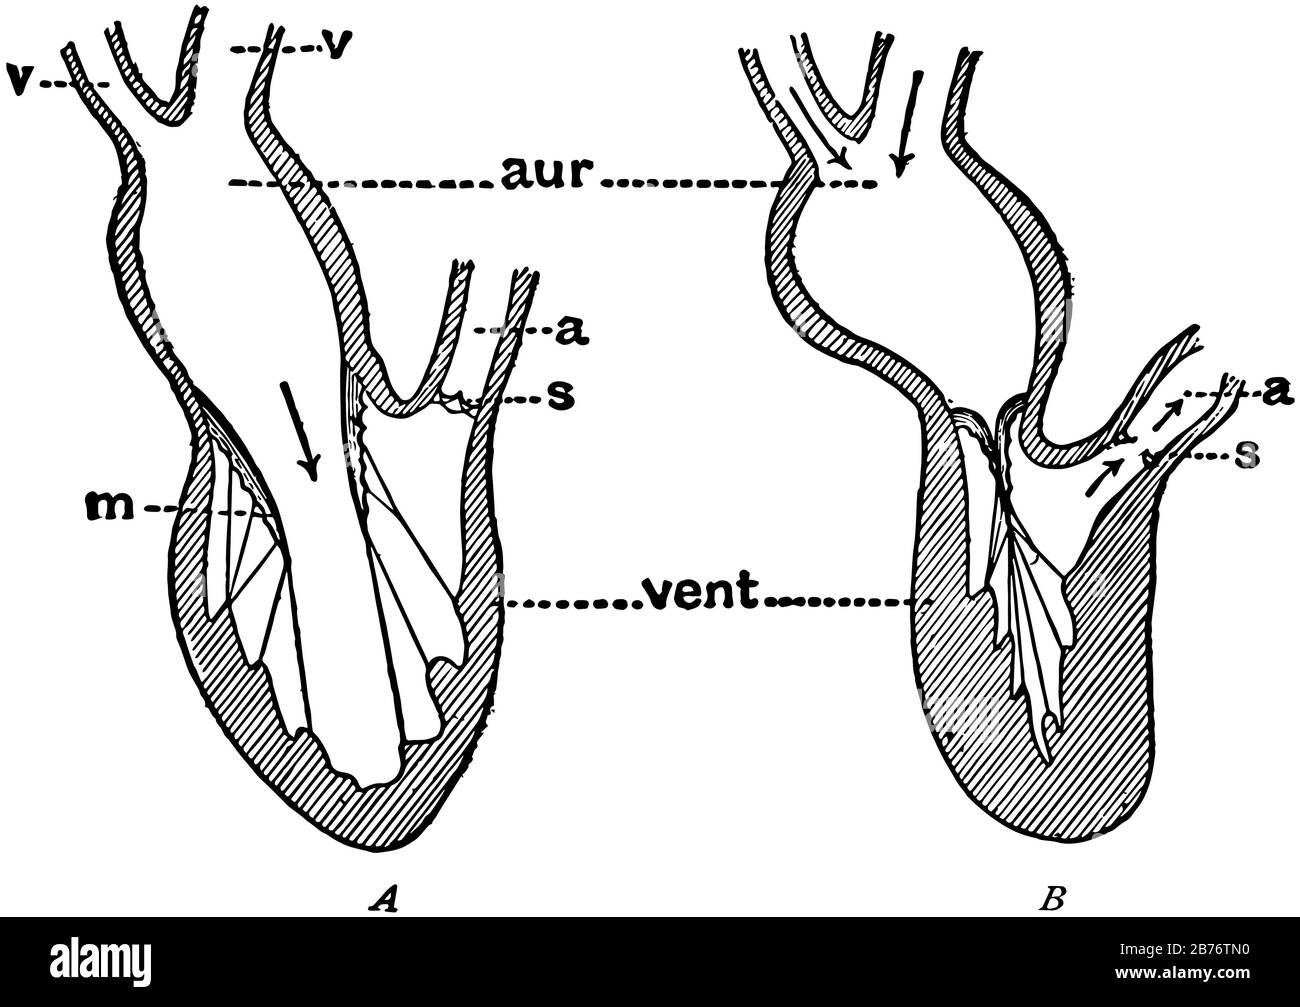

This diagram represents the Pumping of the Heart, vintage line drawing or engraving illustration. Stock Vectorhttps://www.alamy.com/image-license-details/?v=1https://www.alamy.com/this-diagram-represents-the-pumping-of-the-heart-vintage-line-drawing-or-engraving-illustration-image348661068.html

This diagram represents the Pumping of the Heart, vintage line drawing or engraving illustration. Stock Vectorhttps://www.alamy.com/image-license-details/?v=1https://www.alamy.com/this-diagram-represents-the-pumping-of-the-heart-vintage-line-drawing-or-engraving-illustration-image348661068.htmlRF2B76TN0–This diagram represents the Pumping of the Heart, vintage line drawing or engraving illustration.